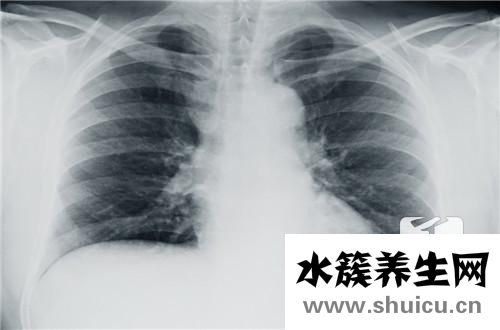

食管癌在醫藥學上又叫食道癌,全是消化道上的惡變腫瘤。假如要談起食管癌早期癥狀,很多人或許都能想起消化系統有關的病癥,此外,胸骨后和劍突下疼痛,是食管癌的早期癥狀在讓你警告。

胸骨后和劍突下疼痛是食管癌較易患的早期癥狀。其特性可呈灼燒樣、扎針樣或伸展樣,主要表現為吞咽食材時有胸骨后或劍突下痛,以吞咽不光滑、炙熱或有含有刺激性的食物為著。疼痛多可被解痙劑臨時減輕。始初呈間斷性,當癌瘤侵犯到周邊組織或有透過時,就會有強烈而持續的疼痛。疼痛位置常不徹底與食道內變病位置一致。

極少數患者可有胸骨后悶脹不適感、前痛和喛氣等病癥。